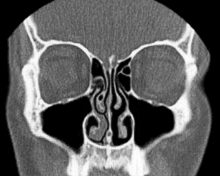

Normal Nose CT Front cross section